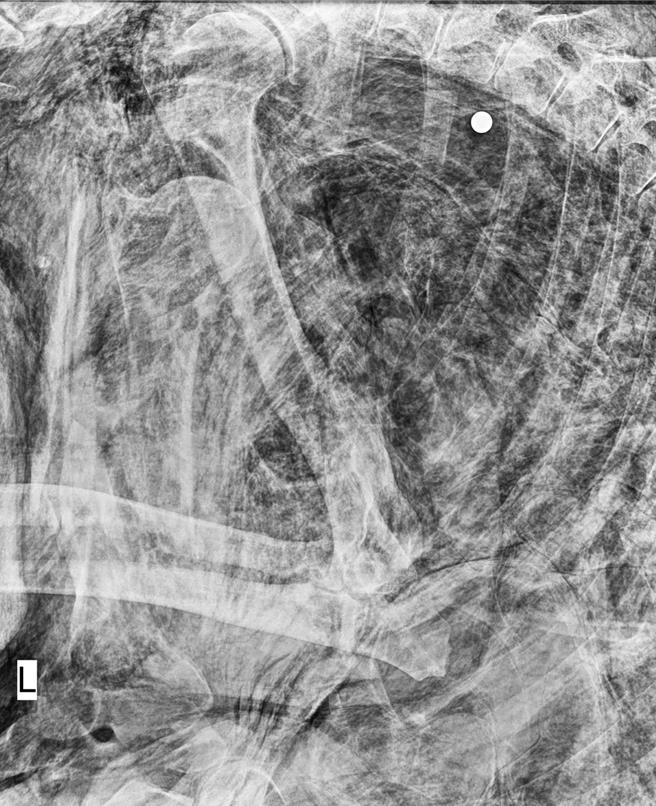

遭枪杀的台湾黑熊,经解剖发现子弹卡在左侧胸腔背侧,至少死亡3天以上。(玉山国家公园提供/杨静茹南投传真)

玉管处将台湾黑熊遗体送往屏东科技大学兽医系动物疾病诊断中心解剖,发现牠的左侧胸腔背侧检验出致死之子弹。根据遗体腐烂状态推断,该只黑熊发现时已死亡3日以上,其陈尸位置距国家公园边界仅300公尺,怀疑牠遭民眾夜间盗猎时误杀。